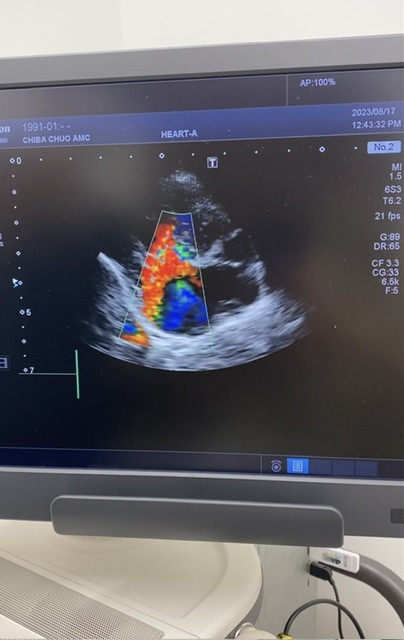

・心エコー

相変わらずの血液検査の逆流

前回と大きく変化はなし